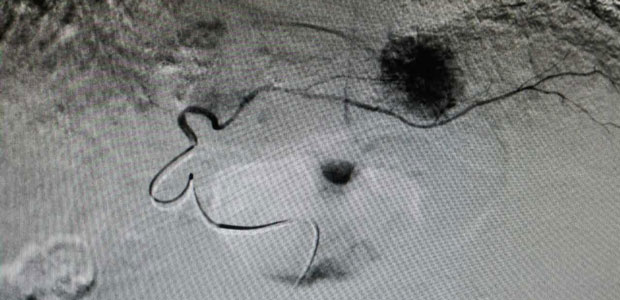

During the operation, the doctor firstly conducted femoral artery puncture with local anaesthesia to patient., channeling the front end of catheter into celiac artery, proper hepatic artery and arteries on both left and right liver to detect the tumor lesion.

Secondly, the doctor identified each supplying artery by catheter and performed drug injection and embolism.